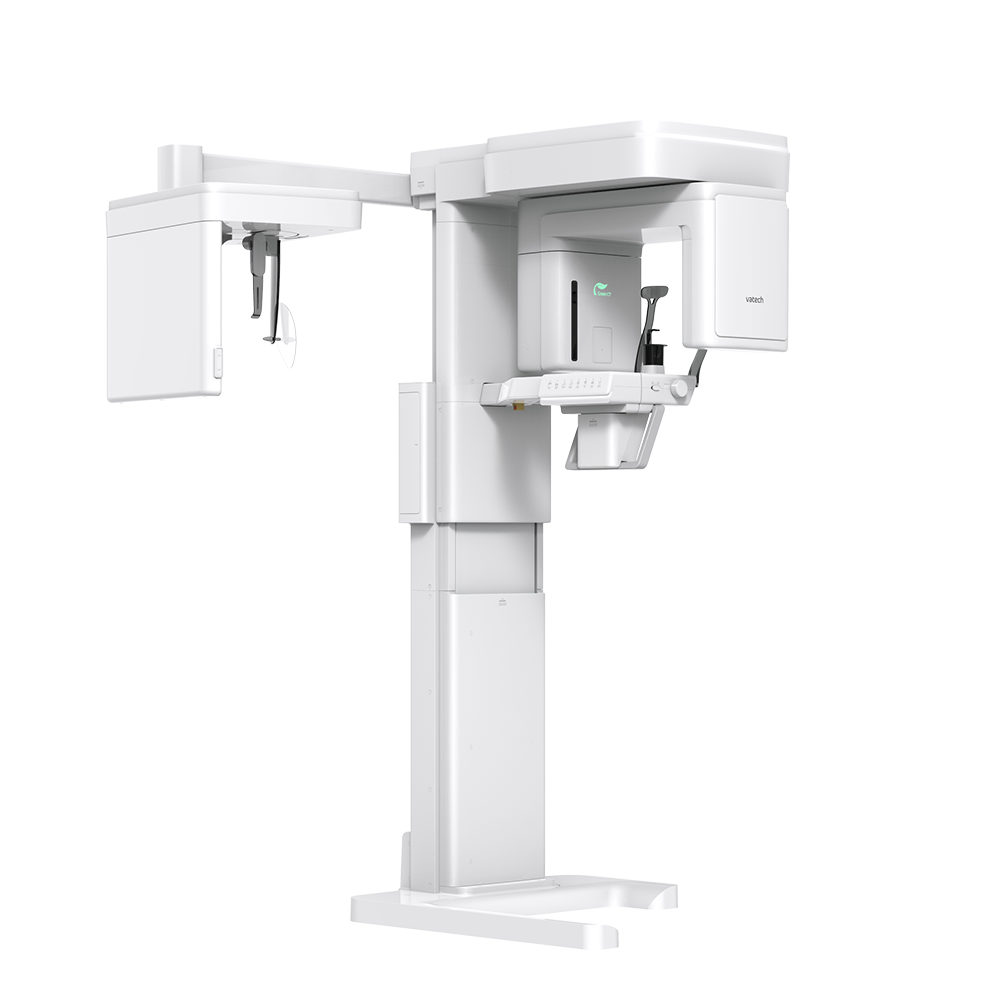

CBCT GREEN X

CBCT GREEN X, produs de VATECH, reprezintă o soluție completă și inovatoare pentru investigațiile 2D și 3D în domeniul medicinei dentare.